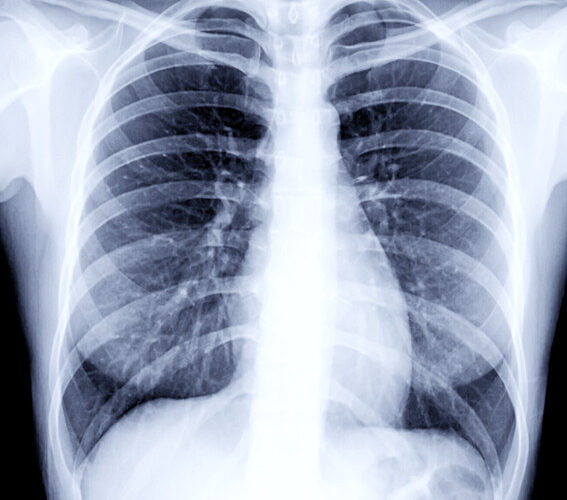

छातीमा देखिने दाग भनेको के हो ? जान्नुहोस्

नेपालमा प्रचलित भनाइ छ — “वैदेशिक रोजगारीमा जान मेडिकल पास हुनुपर्छ”। तर मेडिकल रिपोर्टमा “Chest scar” वा “छातीमा दाग” लेखिएपछि धेरैले आफ्नो सपना त्याग्नुपरेको छ। आखिर यो दाग भनेको के हो? किन यति धेरै समस्याको कारण बन्छ? र यसबाट कसरी बच्न सकिन्छ?

छातीमा दाग भन्नाले के बुझिन्छ?

वैदेशिक रोजगारीको लागि अनिवार्य हुने स्वास्थ्य परीक्षणमा Chest X-ray गरिन्छ। यसमा फोक्सो (lungs) को अवस्था हेर्ने गरिन्छ।

छातीमा दाग भन्नाले प्रायः फोक्सोमा पुरानो रोग, संक्रमण वा चोटपटकपछि बाँकी रहेको ‘scar’ (घाउको निशान) लाई जनाउँछ। यो दाग प्रायः सामान्यतया मानिसलाई थाहा नहुने गरी हुन्छ र X-ray गर्दा मात्र देखिन्छ।